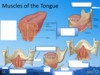

What are the two parts to the tongue? How big are they?

What are the intrinsic muscle layers of the tongue (from superior to inferior)?

Superior longitudinal, vertical, transverse, inferior longitidinal.